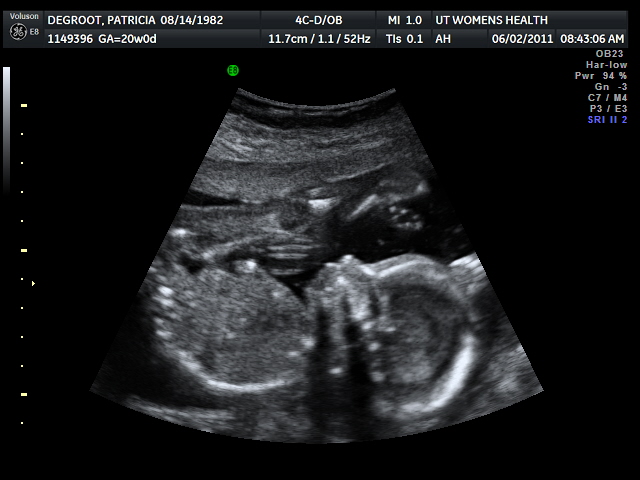

| This was particularly fun to watch...baby was playing with his/her toes! |